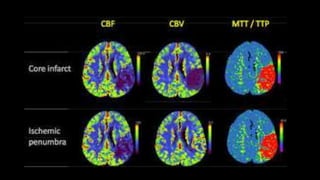

CBV

Cerebral blood volume

CBF

Cerebral blood flow

MTT

Mean transit time

TTP

Time to peak

Core infarct Pattern:

• CT: MTT - CBF - CBV.

• Penumbra pattern:

• CT : MTT - CBF - CBV.